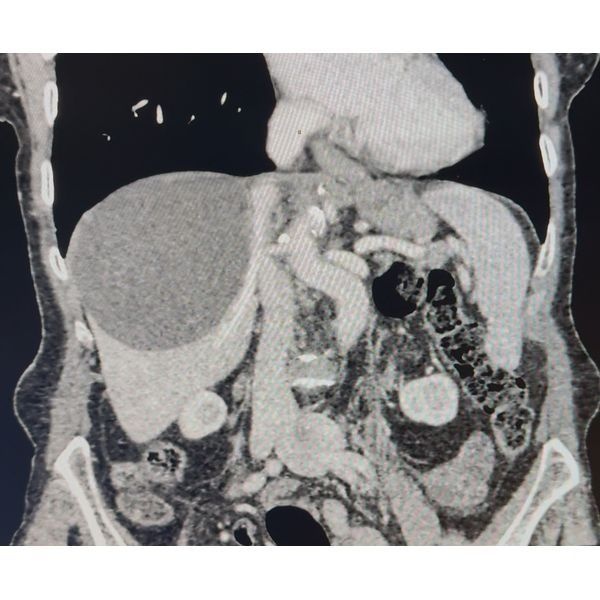

Однако УЗИ органов брюшной полости выявило гигантскую кисту неправильной формы диаметром 98 мм в правой доле печени. Внутри кисты определялось неоднородное подвижное содержимое без кровотока. При этом внутрипечёночные желчные протоки оставались нерасширенными, свободной жидкости в брюшной полости не было.

КТ подтвердила наличие гигантской кисты печени.